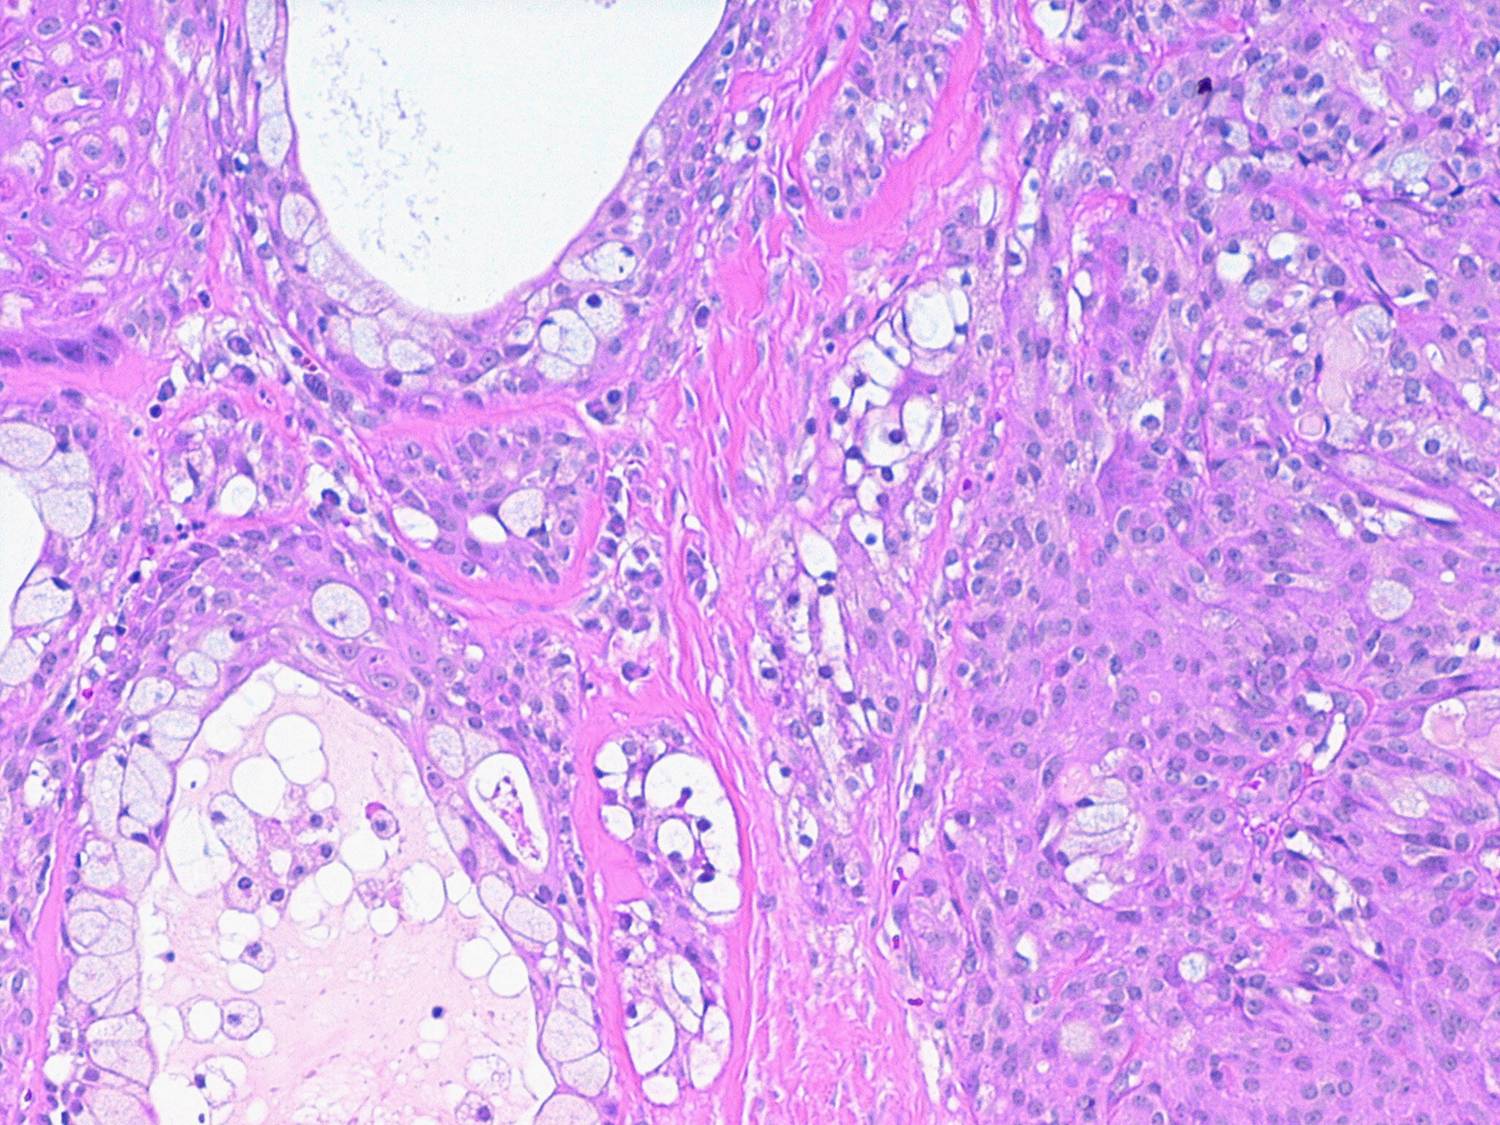

Mucoepidermoid carcinoma =الكارسينوما المخاطية البشروانية